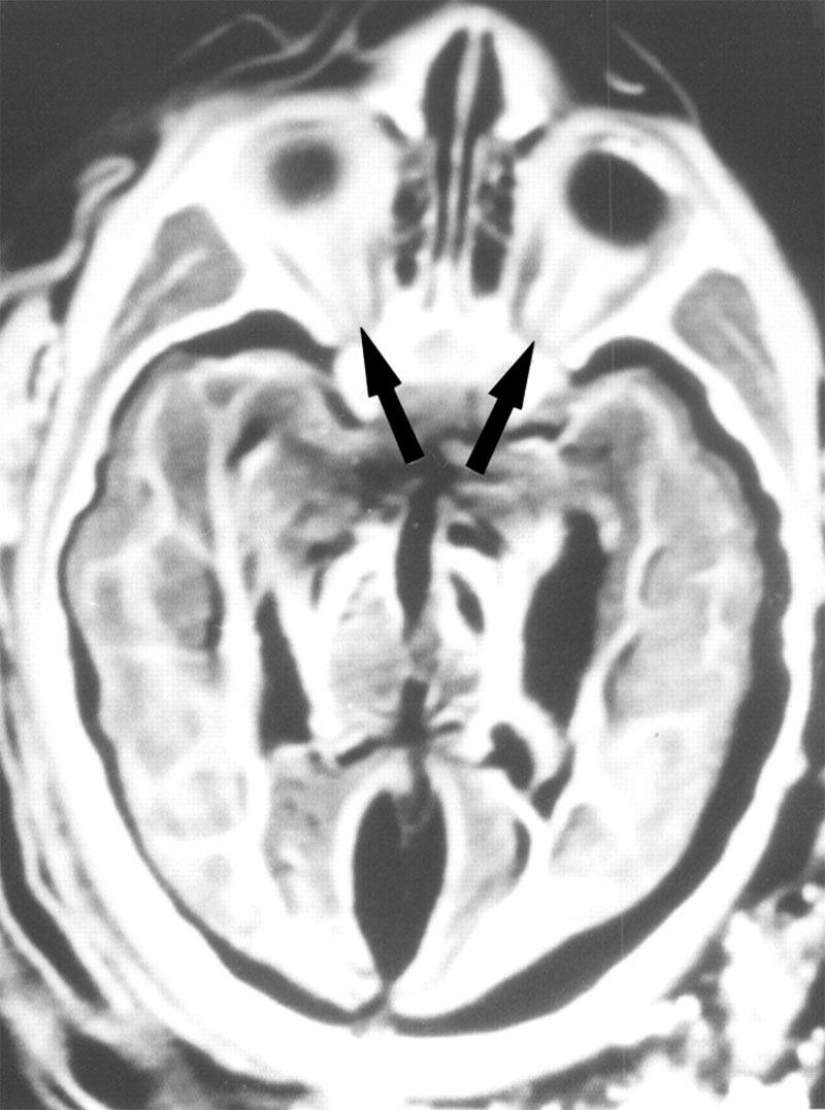

5. Los rayos X del cerebro, de 6 años, niña mostró que ella fue golpeada por un rayo. Aquí se muestra que las órbitas de los ojos, los nervios ópticos (flechas) y la óptica de los músculos.